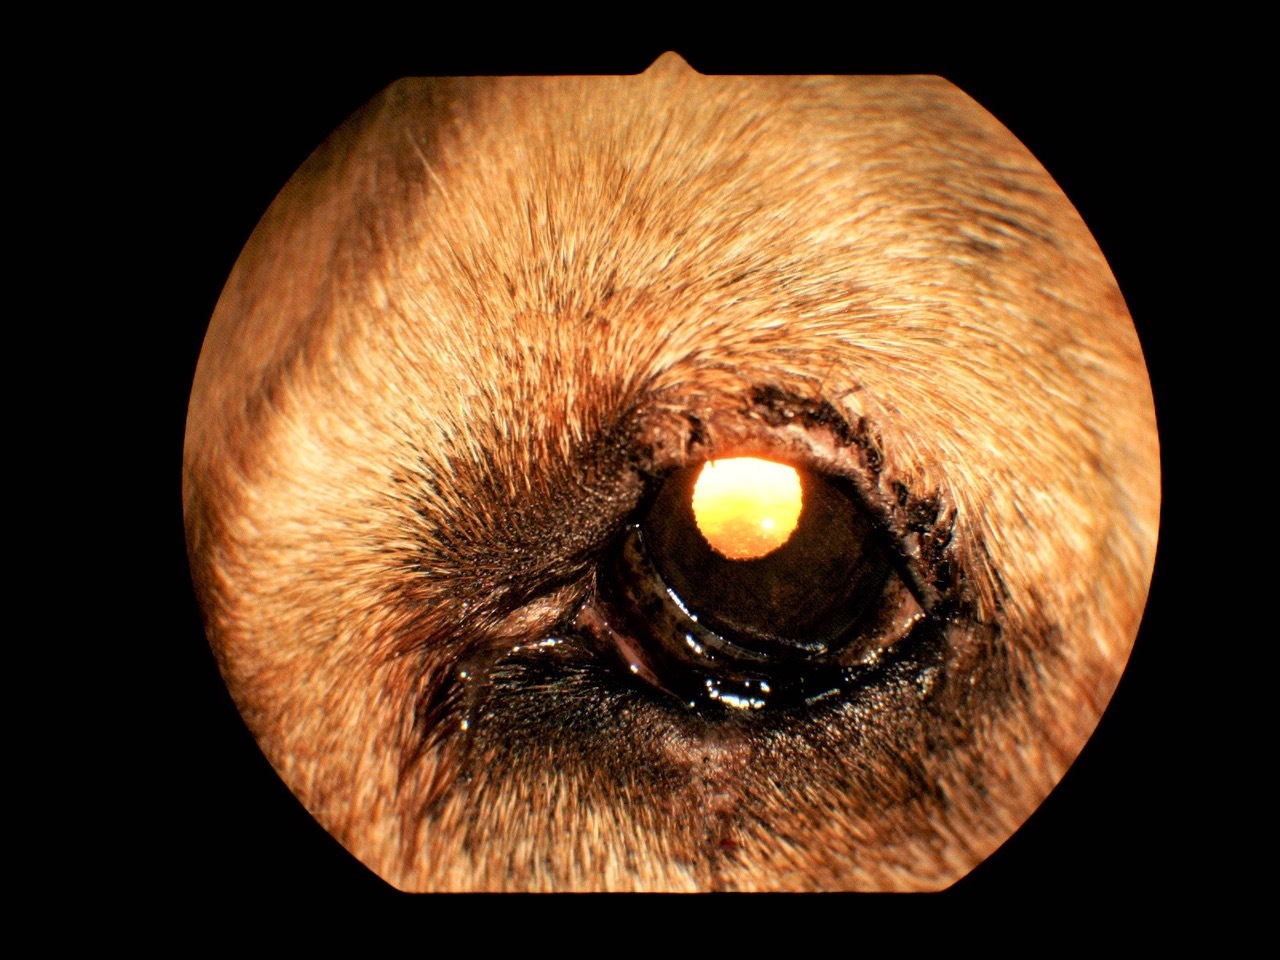

„Murphy“ hat nach der Operation in den ersten 14 Tagen weiterhin Augensalben und -tropfen bekommen, damit der Hornhautdefekt abheilen konnte. Zusätzlich erhielt er für einige Tage antibiotische und entzündungshemmende Tabletten, um Infektionen zu vermeiden und den Wundschmerz zu mindern. Vorsichtshalber wurde ihm in den ersten Tagen auch ein Kratzschutz in Form eines Halskragens verpasst. Nach 14 Tagen waren die Wunden gut verheilt und die Fäden konnten gezogen werden (Abb. 4 und 5). Das Ergebnis vom Lidlifting: „Murphy“ kann beide Augen wieder gut öffnen, normal schließen, ist schmerzfrei und hat endlich wieder den vollen Durchblick (Abb. 6).